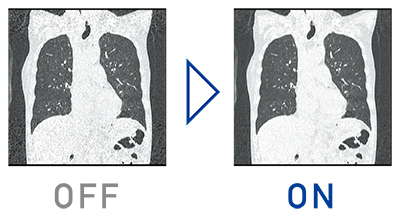

特長<1>

逐次近似処理をルーチン検査に

逐次近似処理をルーチン検査で使いやすくする為に,画像処理速度を50%向上させ,ノイズ低減の強度も7段階から選択できます。適切な被ばく線量と,画像ノイズなどの低減による高画質な画像を提供します。